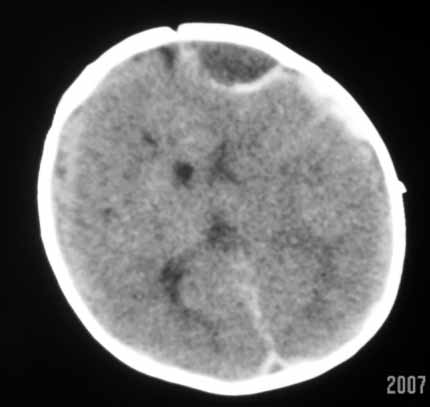

标题: PED0294: 2月婴儿.VitK缺乏症颅内出血.. [打印本页]

标题: PED0294: 2月婴儿.VitK缺乏症颅内出血..

可见 硬膜下及硬膜外血肿,蛛网膜下腔出血

以下是引用jiangjing在2007-8-2 15:07:00的发言:[br]可见 硬膜下及硬膜外血肿,蛛网膜下腔出血

vk缺乏症ct表现有脑实质内出血,珠网膜下腔,硬膜下出血,硬膜外出血,脑实质内出血少见。本病出血要点出血量大,多部位出血,脑室质出血呈团快状。